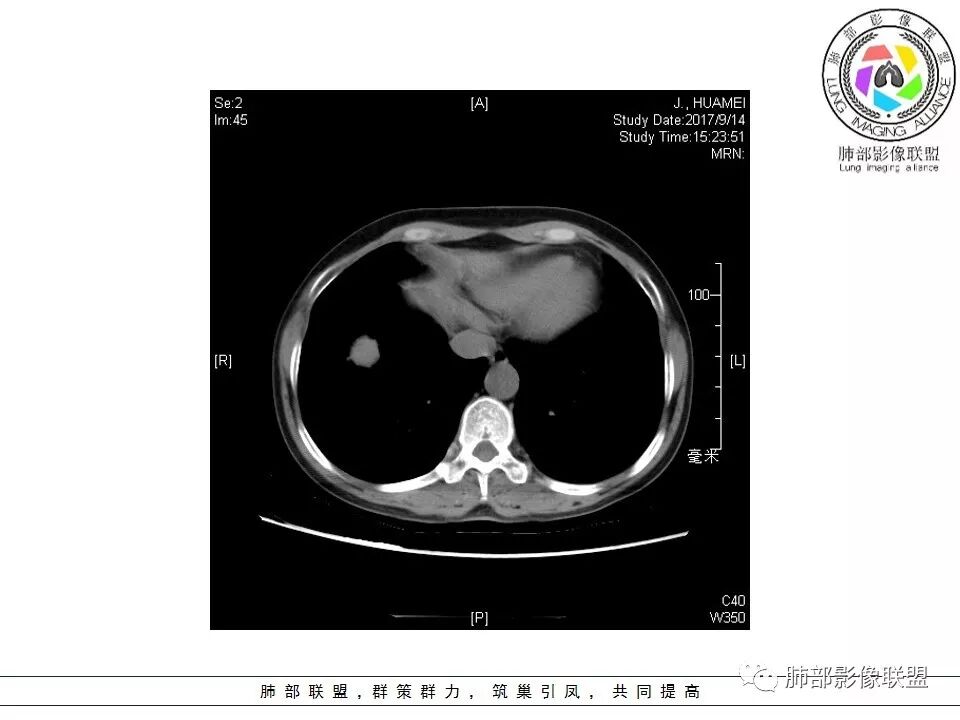

晨读:右肺下叶肿块影,浅分叶,不均匀强化,有血管穿行其中,考虑肺癌,神经内分泌肿瘤可能性大。

右肺下叶结节,边缘毛糙,内支气管推移,有血管贴行,小细胞肺癌?

晨读:右下肺前基底段支气管亚段分叉处占位,密度均匀、中度均匀强化,结节近边缘有支气管、血管穿行,结节边缘较光滑、有细短毛刺、无分叶,结节周围无卫星灶。考虑:PSP,鉴别:小细胞肺癌、不典型错钩瘤

内部支气管扩张,穿行血管形态自然,支持malt。

轻度分叶,支气管穿行,轻中度强化,血管漂浮,考虑MALT

右肺下叶前基底段肿块,边缘不光滑,毛糙,内见充气支气管征,边缘有浅分叶,肿块周围无病灶,排除了结核。增强扫描明显强化,内见血管影,考虑恶性肿瘤。女性,腺癌多见。

淋巴瘤与小细胞癌鉴别,纵隔内没有肿大淋巴结、结节边缘比较毛糙,淋巴瘤放第一位。

病灶呈圆形,轻度分叶,内见血管及支气管影,考虑MALT。

右肺下叶前基底段结节 边缘磨玻璃密度较清 内部支气管扩张,轻中度强化 穿行血管形态自然,支持淋巴瘤。

晨读:右肺下叶肿块影,浅分叶,边界清,轻度均匀强化,血管自然穿行,NSE偏高,考虑小细胞肺癌!

中年女性,右肺下叶前基底段肿块,轻度分叶,有棘样突出,充气支气管征穿行并形成脐凹征。增强扫描中度强化,内见血管影,血管壁毛糙,考虑恶性,腺癌?小细胞肺癌?

晨读,右肺下叶前基底段实性结节,边缘膨隆,可见多发浅分叶,结节内密度均匀,增强后呈轻度均匀强化,血管穿行走形自然,首先考虑恶性肿瘤,内有支气管穿行,淋巴瘤可能大,腺癌待排。

右肺下叶肿块,边缘光滑,浅分叶,膨隆明显,局部有清楚的ggo,考虑恶性,类癌首可能,鉴别腺,PSP。

中年女性,右下类圆形肿块,部分膨胧,边缘浅分叶,脐凹,内见血管穿行,增强轻中度强化,叶间胸膜结节?考虑腺癌,内有支气管穿行,鉴别淋巴瘤。

右肺下叶肿块影,边缘光滑,彭隆,浅分叶,内见支气管通过,增强明显强化,内见血管影,考虑恶性肿瘤,神经内分泌癌,鉴别淋巴瘤。

中年女性,体检发现,病史及化验无特殊。胸部CT右肺下叶前基底段见一类圆形结节,边界清楚,分叶不明显,边缘呈锯齿状改变,病灶内支气管穿行,无扩张及扭曲,增强扫描病灶明显均匀强化,内见穿行血管影,走形无扭曲。考虑粘膜相关性淋巴瘤可能。鉴别炎性假瘤、腺癌及小细胞癌。

胸CT:右肺下叶前基底段占位性病变,内可见支气管穿过,病灶边缘不规则,呈浅分叶,未见明显毛刺。纵隔窗可见病灶密度相对均匀,增强可见病灶强化,内可见血管增粗,边缘模糊,总体考虑恶性,腺?。良性疾病鉴别错构。

右下肺类圆形实形结节,边缘膨隆,浅分叶,其内可见支气管及血管影走行,轻度强化,考虑恶性病灶,淋巴瘤?类癌?

边缘彭隆,还是考虑肿瘤,支气管通入,肺内原发,支气管自然穿行稍扩张,血管比较自然同行,漂浮征,增强后整个比较均匀无明显坏死,淋巴瘤首选。恶性应该没有问题,建议穿刺。

这个病灶边缘还是有一点点恶性征象,有分叶,似乎有点地方还有一些小毛刺样感觉

部分区域整体以膨隆为主,部分区域稍收缩

内部支气管走形非常自然,达远端稍扩张;内部血管穿行也非常自然

内部密度比较均匀,我们一般来说,首先良性肿瘤不支持,因为它里面的血管走形太自然了;然后就是炎性病变跟恶性肿瘤,但是它的边缘膨隆比较厉害,有些地方还毛刺,不是很清楚,倾向一个恶性病变

恶性的血管穿行自然,包括支气管稍扩张,最常见还是淋巴瘤,它强化比较均匀;

粘液腺癌一般支气管扩张比较罕见,这个密度及强化太均匀,不是很符合,所以把淋巴瘤放前面,癌待排;

方向定在恶性的,炎性病变不是很符合